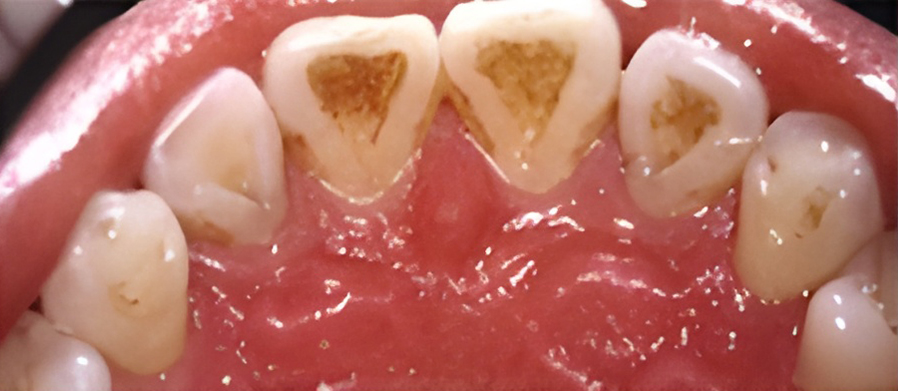

칫솔질과 치실질을 통해 매일 플라그를 제거하지 않으면 박테리아로 인해 잇몸 조직이 붉어지고 부어오르게 됩니다. 염증이 더 심해지면, 치아 주위 조직에 염증이 생기는 치주염으로 진행될 수 있습니다.

보통 치은염은 칫솔질을 꼼꼼하게 열심히 하고 치실을 사용함으로써 건강한 잇몸을 회복할 수 있습니다. 올바른 칫솔질과 정기적인 스케일링으로 세균이 자랄 수 있는 환경을 제거하면 잇몸을 건강하게 유지할 수 있습니다.